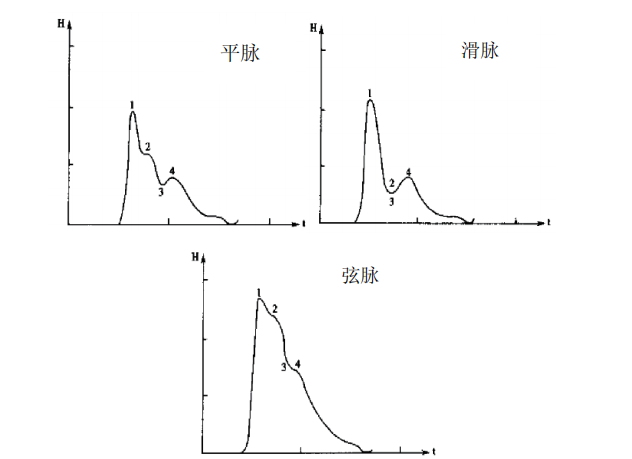

此外,说到这里,大家是不是想起来点什么~没错,那就是中医传统脉诊!脉搏压力压力波脉图,可以与传统的28种脉象建立起联系,比如

平脉、弦脉和滑脉对应于不同的压力脉图 | 图自[5]

(小编不得不感慨一下,自己对着脉搏摸了半天,啥也没摸出来,这种波形差别,真的是人能摸出来的?关键真是。听说学习中医的同学要对着脉象模拟器练习很久,不禁感慨,术业有专攻。)